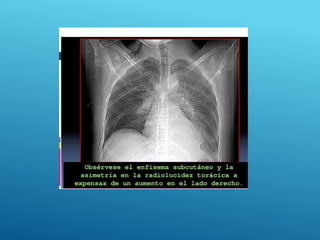

 Buscar presencia de ruidos pulmonares,

 Enfisema subcutáneo,